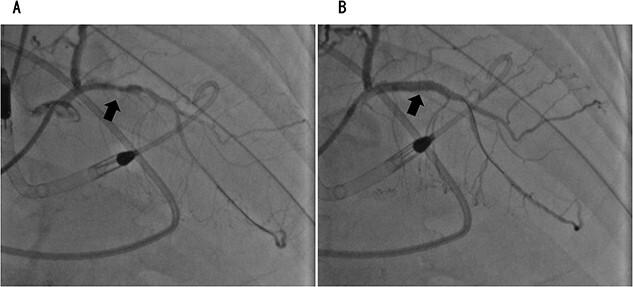

Postoperative hemodynamic support with an Impella 5.0 was effective in a man who underwent lung lobectomy for lung cancer and cardiogenic shock. A 75-year-old man presented to hospital with an abnormal chest shadow on radiography. After thorough examination, the patient was diagnosed with lung cancer, and left lower lobectomy was performed. On the 2nd postoperative day, the patient experienced cardiac arrest because of a sudden drop in saturation of percutaneous oxygen. After a third defibrillation, his heartbeat resumed, and he was intubated and placed on a ventilator. Coronary angiography revealed acute coronary syndrome and the patient fell into a state of shock, which required venoarterial extracorporeal membrane oxygenation (VA-ECMO) support. Nevertheless, the circulatory dynamics are unstable, and Impella 5.0 was introduced. VA-ECMO and the Impella 5.0 were discontinued on the 6th and 8th postoperative days, respectively. The patient was eventually transferred to a nearby facility for further rehabilitation 109 days later.

一名因肺癌接受肺叶切除术并发生心源性休克的男性患者,使用Impella 5.0进行术后血流动力学支持取得了良好效果。一名75岁男性因胸部X光片显示异常阴影入院。经过全面检查,患者被诊断为肺癌,并接受了左下肺叶切除术。术后第2天,患者因经皮血氧饱和度突然下降发生心脏骤停。第三次除颤后,患者心跳恢复,随后进行气管插管并使用呼吸机。冠状动脉造影显示急性冠状动脉综合征,患者陷入休克状态,需要静脉-动脉体外膜肺氧合(VA-ECMO)支持。然而,循环动力学仍不稳定,于是引入了Impella 5.0。VA-ECMO和Impella 5.0分别在术后第6天和第8天停用。最终,患者在109天后被转至附近机构进行进一步康复治疗。